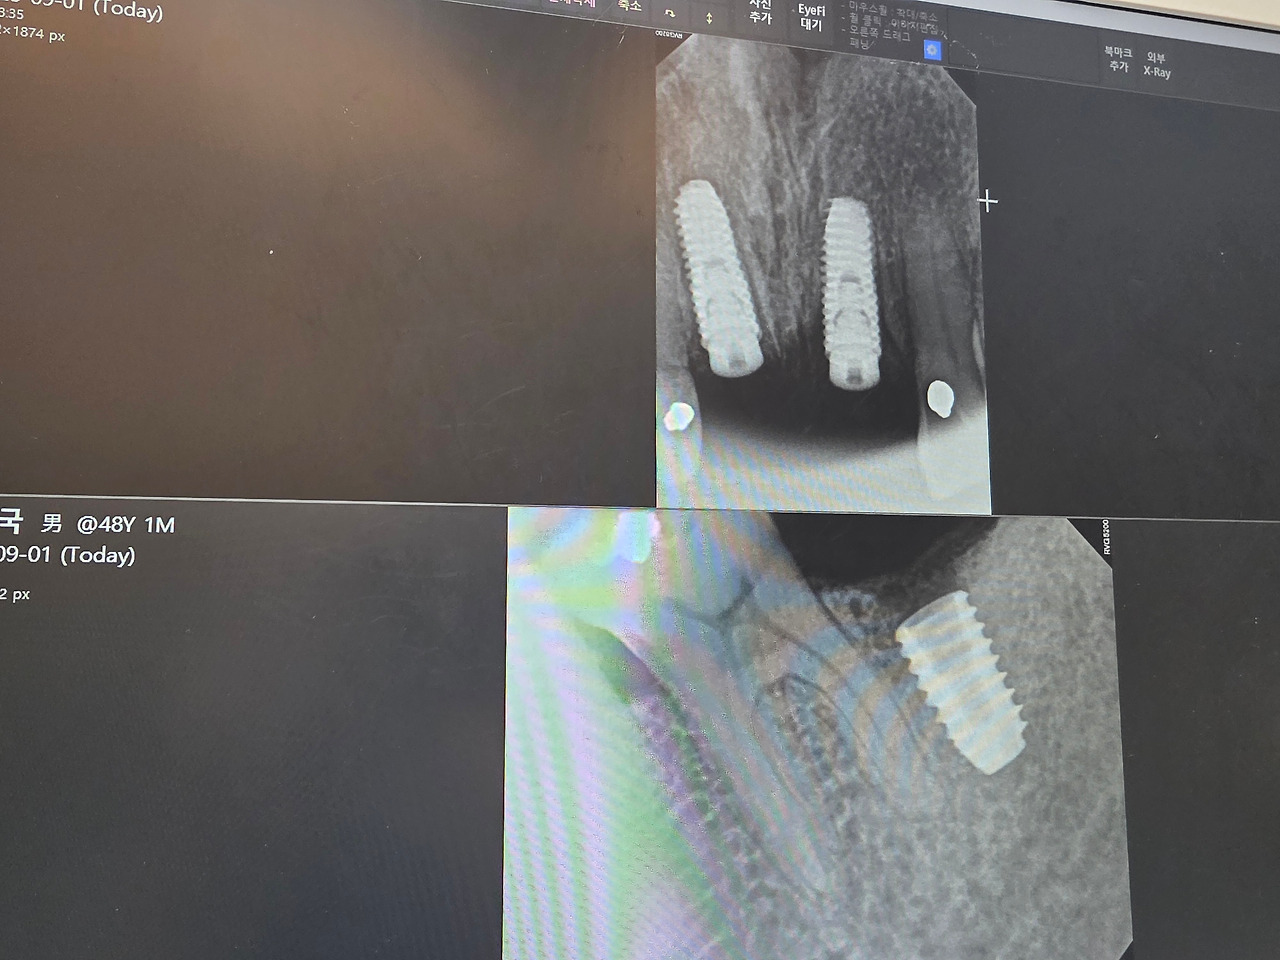

정밀 진단 : 3D CT 촬영으로 잇몸뼈의 두께와 신경 위치를 파악하고, 컴퓨터 가이드 수술 계획을 세웠다.

정밀 수술 기기 : 디지털 내비게이션 시스템을 통해 정확한 위치에 식립이 가능했다. 이는 수술 시간을 단축하고, 회복 속도를 빠르게 해 주었다.

통증 관리 : 수술 중 체계적인 마취와 사후 관리로 불편함을 최소화했다.

시술 후 붓기와 통증은 예상보다 훨씬 적었고, 일상 복귀도 빠른 편이었다. “임플란트 수술이 이렇게 달라질 수 있구나”라는 생각이 들 정도였다.